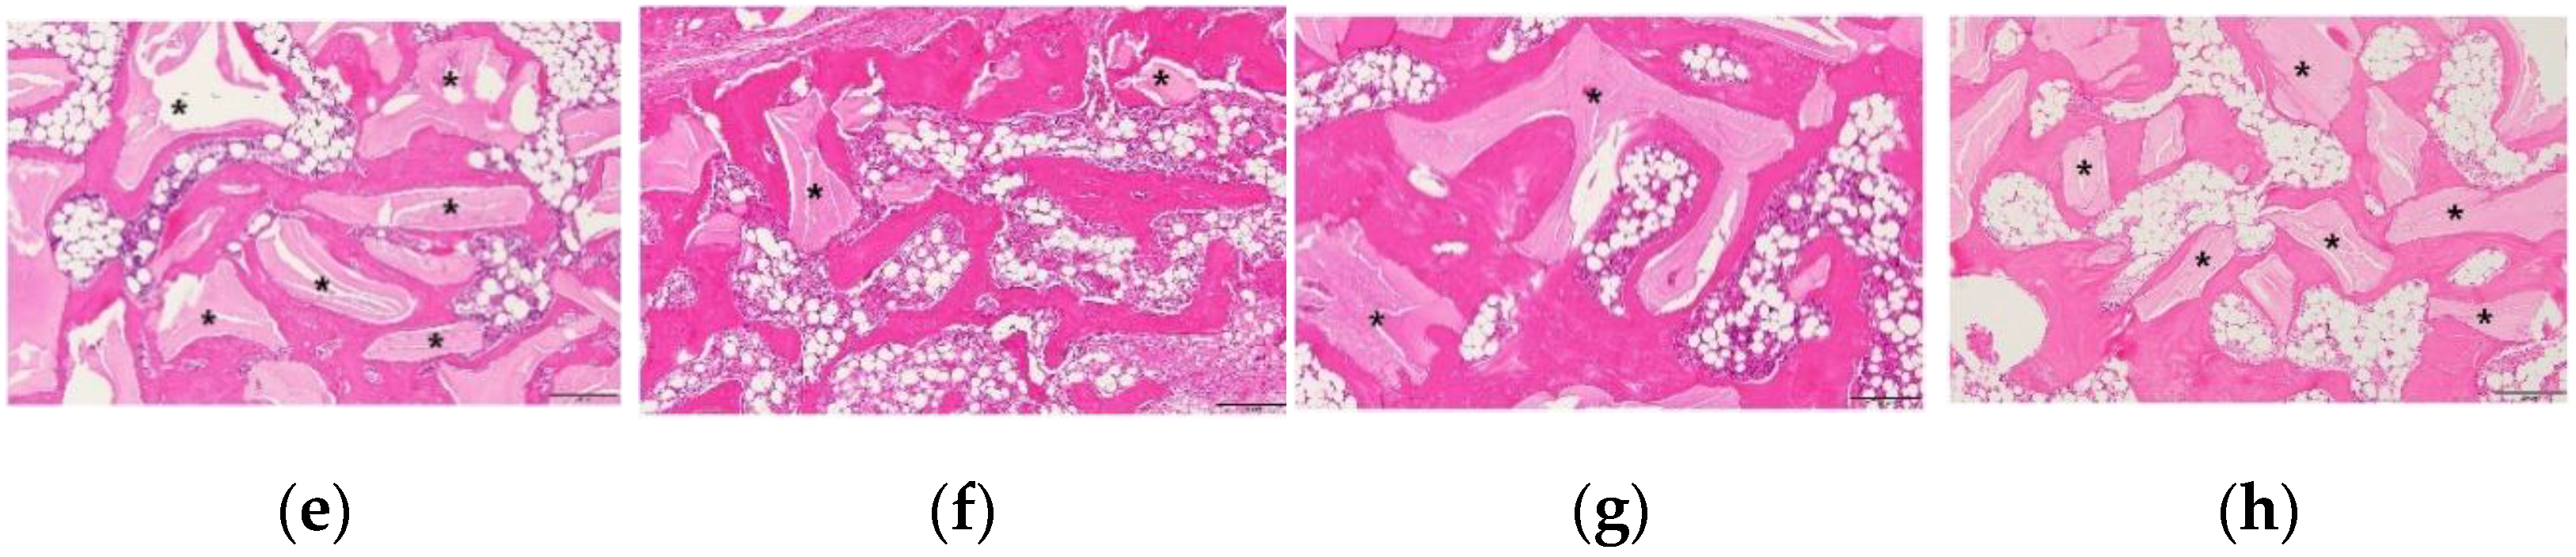

3.3. Histological Examination of the Changes in the Newly Formed Bone and Adipose Tissue